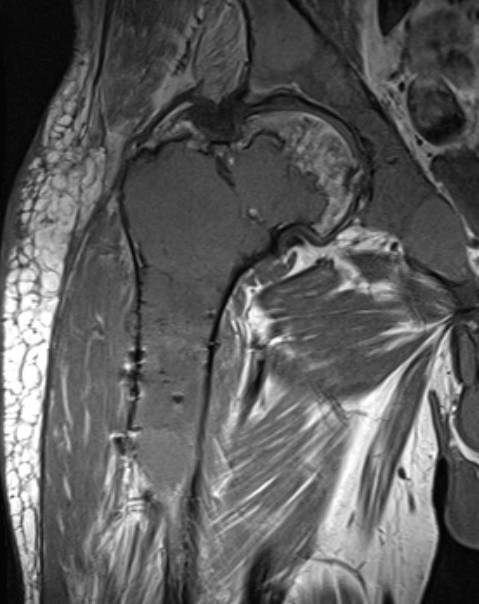

MRI

Low signal intensity T1 / High signal intensity T2

Corrective osteotomy / Intra-medullary nailing

Mainstay of treatment